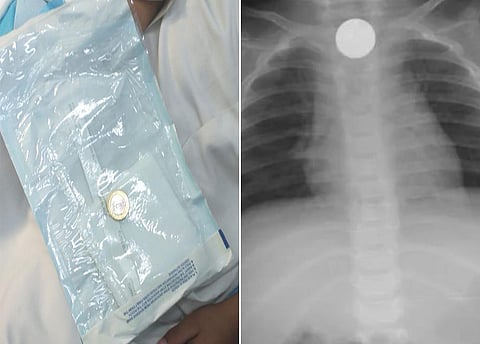

نجح فريق طبي بمستشفى المهد العام في استخراج قطعة معدنية من أعلى مريء طفل يبلغ من العمر ست سنوات، في عملية استغرقت أربع دقائق.

وكان ذوو الطفل أوصلوه لطوارئ المستشفى إثر ابتلاعه جسمًا غريبًا عَلِق في أعلى المريء؛ ما تَسَبّب له في اختناق وعدم قدرة على البلع؛ فيما قرر الفريق الطبي إجراء عملية عاجلة للحالة، حيث اتضح أنها قطعة معدنية نقدية فئة الريال؛ وتمت العملية بنجاح دون حدوث مضاعفات؛ وغادر الطفل المستشفى وهو بصحة جيدة.